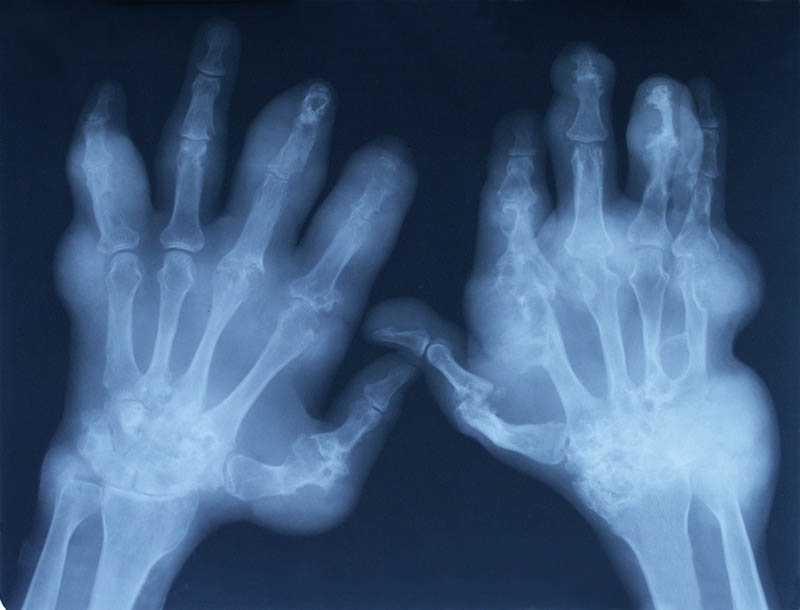

Рентгенологическое исследование кистей рук является неинвазивным методом исследования внутренней структуры костных тканей. Пальцы считаются сложными анатомическими частями тела, состоящими из большого количества мелких костей, и выполняют крайне важную роль в привычном функционировании человека.

Наши руки каждый день подвергаются значительным механическим нагрузкам, поэтому неудивительно, что рано или поздно появляются какие-либо проблемы. Для получения точной картины их состояния необходимо сделать рентгеновский снимок кисти, на котором точно будут видны патологические процессы, переломы, вывихи и трещины. Именно своевременное использование современных диагностических методов предупреждает развитие тяжелых заболеваний.

Каждый день человеческий скелет подвергается интенсивным нагрузкам. Это один из провоцирующих факторов, наряду с травмами и инфекционными заболеваниями, который приводит к изменению структуры костной ткани. Кисти рук часто наиболее уязвимы перед нагрузками, что может привести к частичной или полной потере функциональности.

Для своевременной диагностики патологий используется рентген кисти человека. Суть этого метода предельно проста: пучки рентгеновских лучей проходят через предмет, оставляя контурный след на пленке.

Так что показывает рентген кисти? На снимке специалист может увидеть:

- Различные изменения в мышцах, сухожилиях и лимфатических узлах.

- Воспалительный процесс.

- Вывихи.

- Трещины, микротрещины и истончение костей.

- Общее состояние всех отделов кисти: фаланг пальцев, запястье и пясть.

Рентгеновский снимок кисти оказывается очень информативным именно в определении повреждений костных тканей. Если клинический случай требует более детальной диагностики мягких тканей, то врач может принять решение о проведении компьютерной томографии.

Какие нарушения показывает снимок рентгена?

Мы уже рассказали о том, зачем делать рентген кистей рук – для своевременного выявления патологических процессов, постановки диагноза и назначения дальнейшего лечения. Вот основные нарушения, которые врач может увидеть на снимках:

- Синовит. Эта патология диагностируется по расширенной суставной щели.

Суть этого заболевания заключается в скоплении жидкости в суставе. - Кальцификаты. Эти образования указывают на развитие артрита кистей рук.

- Эрозия. Один из симптомов полиартрита. Его это нарушение диагностируется, то это значит, что болезнь уже перешла в хроническую стадию.

- Остеопороз. Диагностируется по истончению кортикального слоя короткотрубчатых костей. Также является симптомом полиартрита.

- Остеофиты. Это различные костные разрастания на поверхности самих суставов.

- Кисты. Эти новообразования чаще всего локализуются в центральном отделе костного эпифиза.

Эффективность проведения рентгена кистей рук при ревматоидном артрите

Ревматоидный артрит считается одним из наиболее распространенных патологий, поражающих кисти рук. Это аутоиммунное заболевание, характеризующееся поражением соединительной ткани. Если не проводить соответствующую терапию, то существует большой риск инвалидности человека. Поэтому крайне важно своевременное проведение рентгена кистей рук при ревматоидном артрите. Эта процедура позволяет выявить не только само заболевание, но и его стадию.

Он назначается при наличии следующей симптоматики:

- Скованность движений.

- Наличие покраснений и припухлостей.

- Ревматоидные узлы.

- Симметричное поражение суставов.

- Деформация кистей.

- Усиление болей именно в ночное время суток.